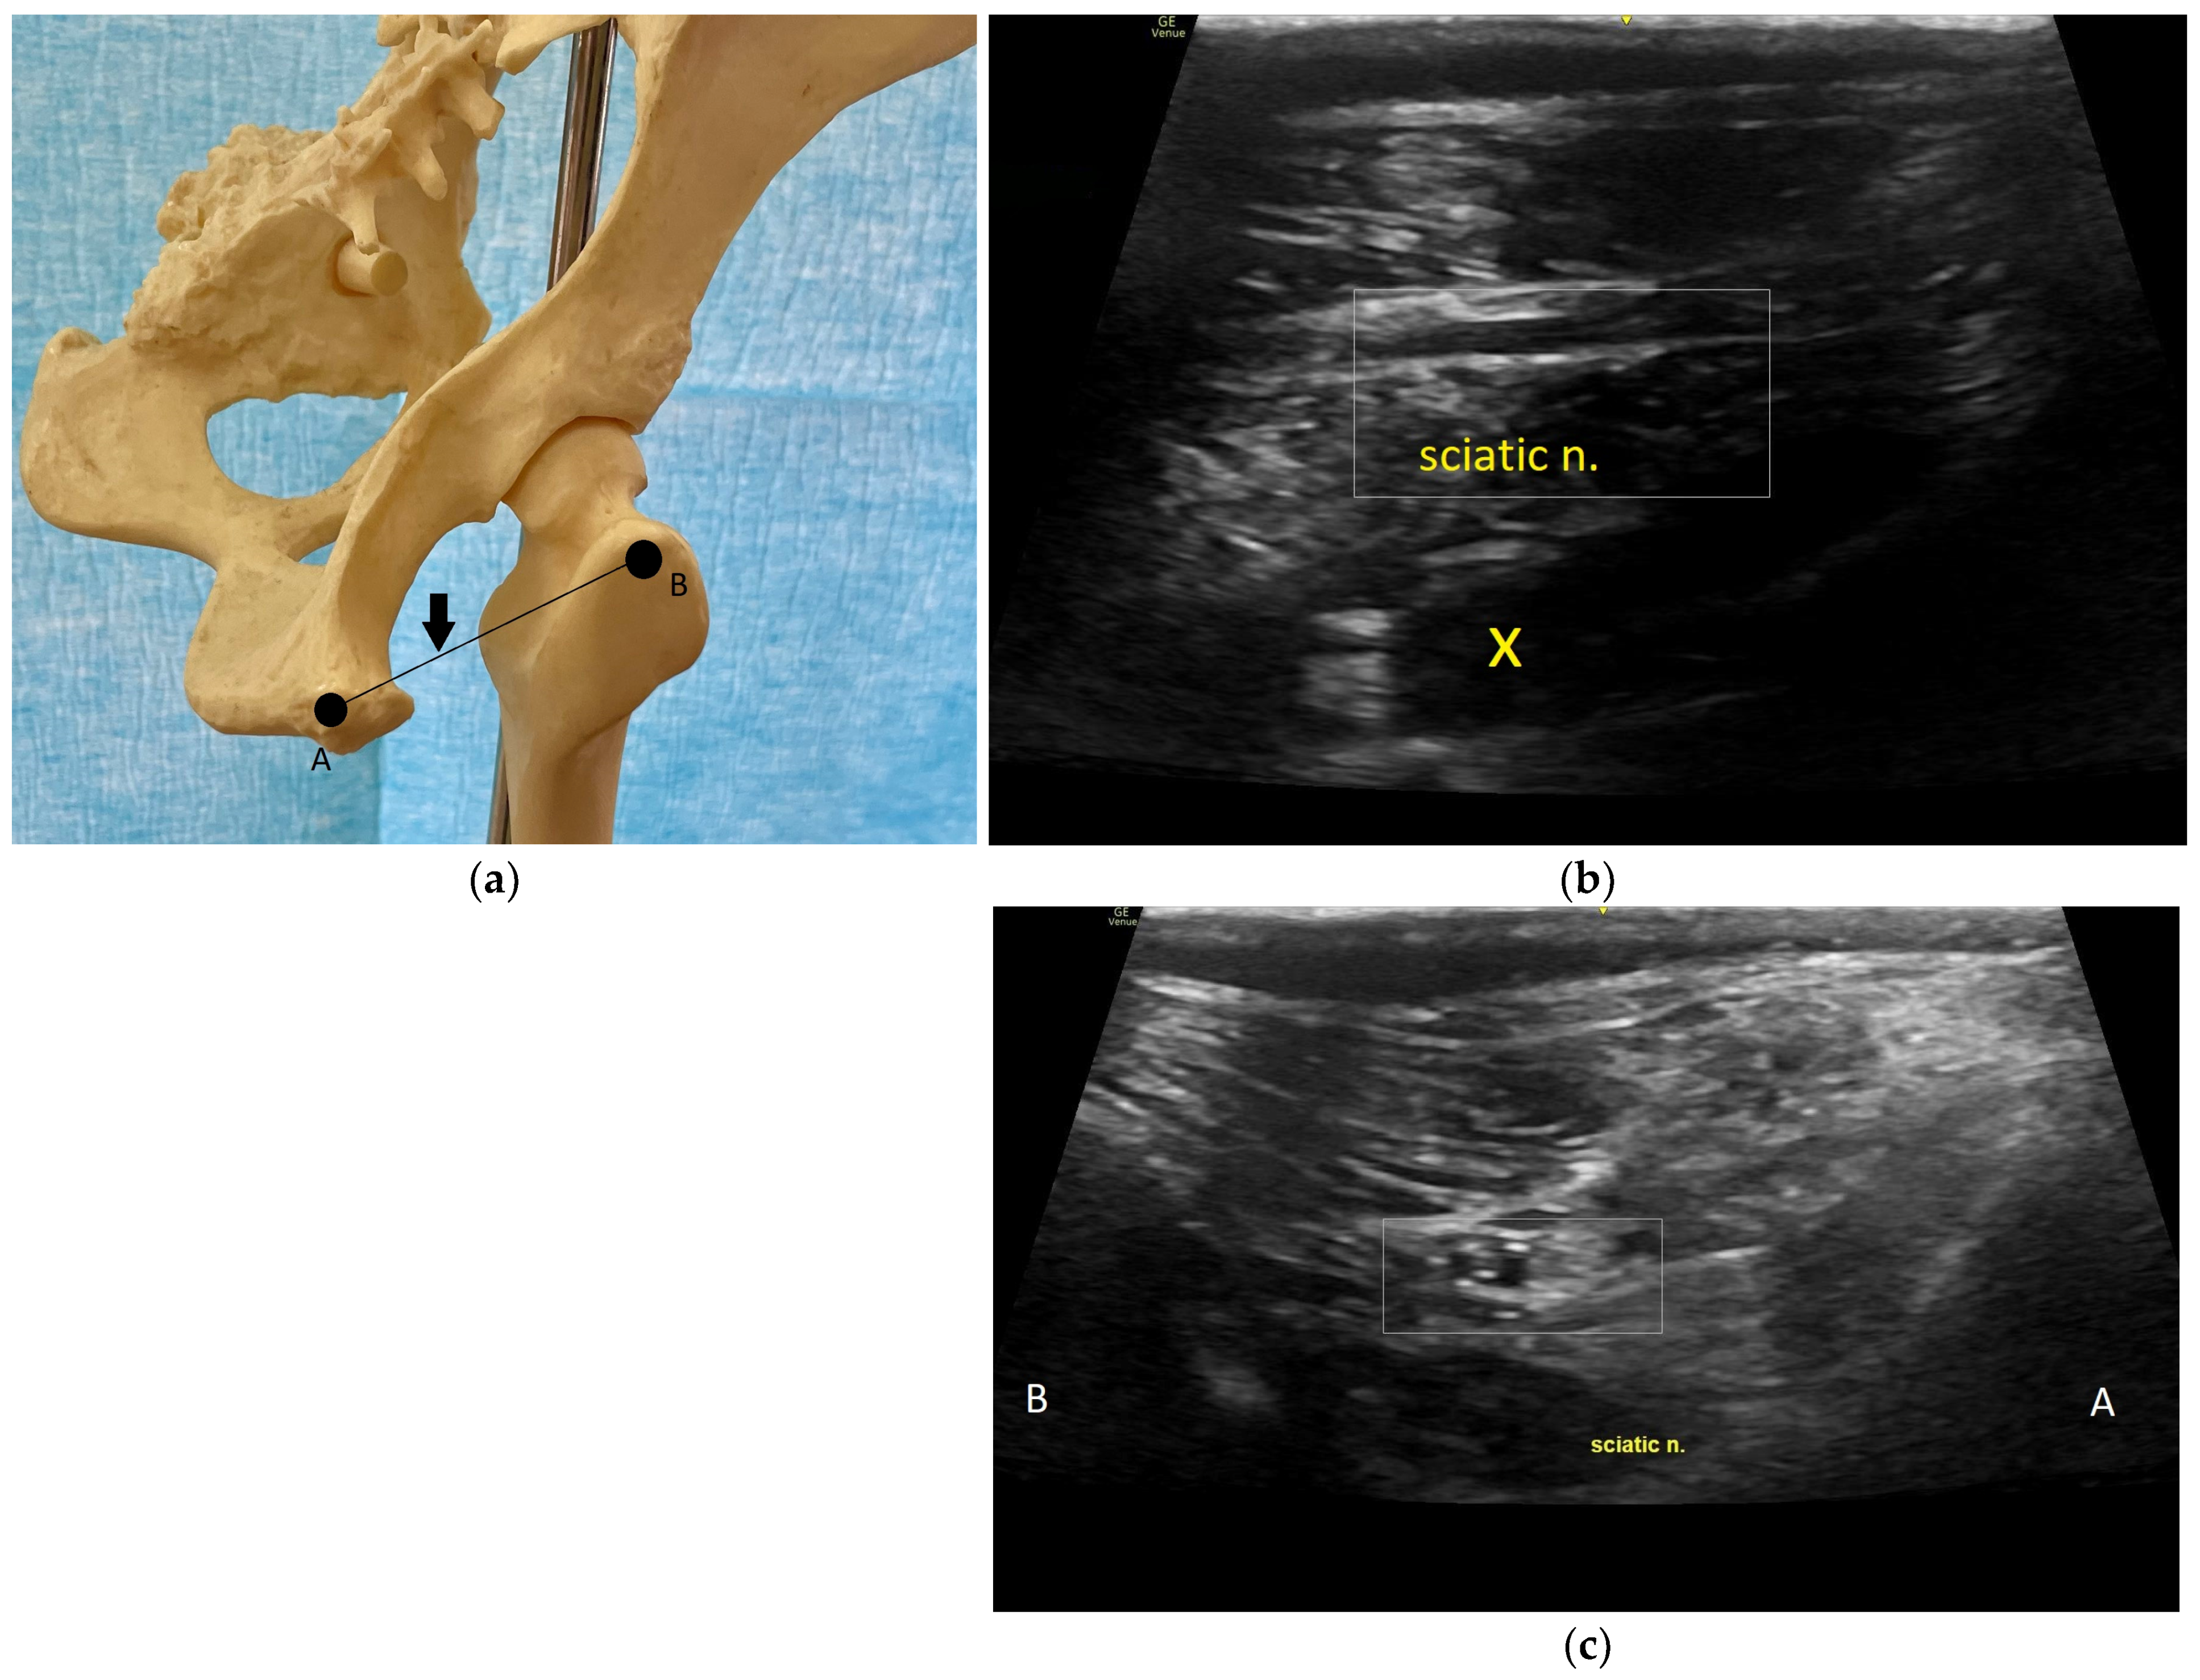

8.2. Sciatic Nerve

8.3. Tibial and Common Peroneal Nerve